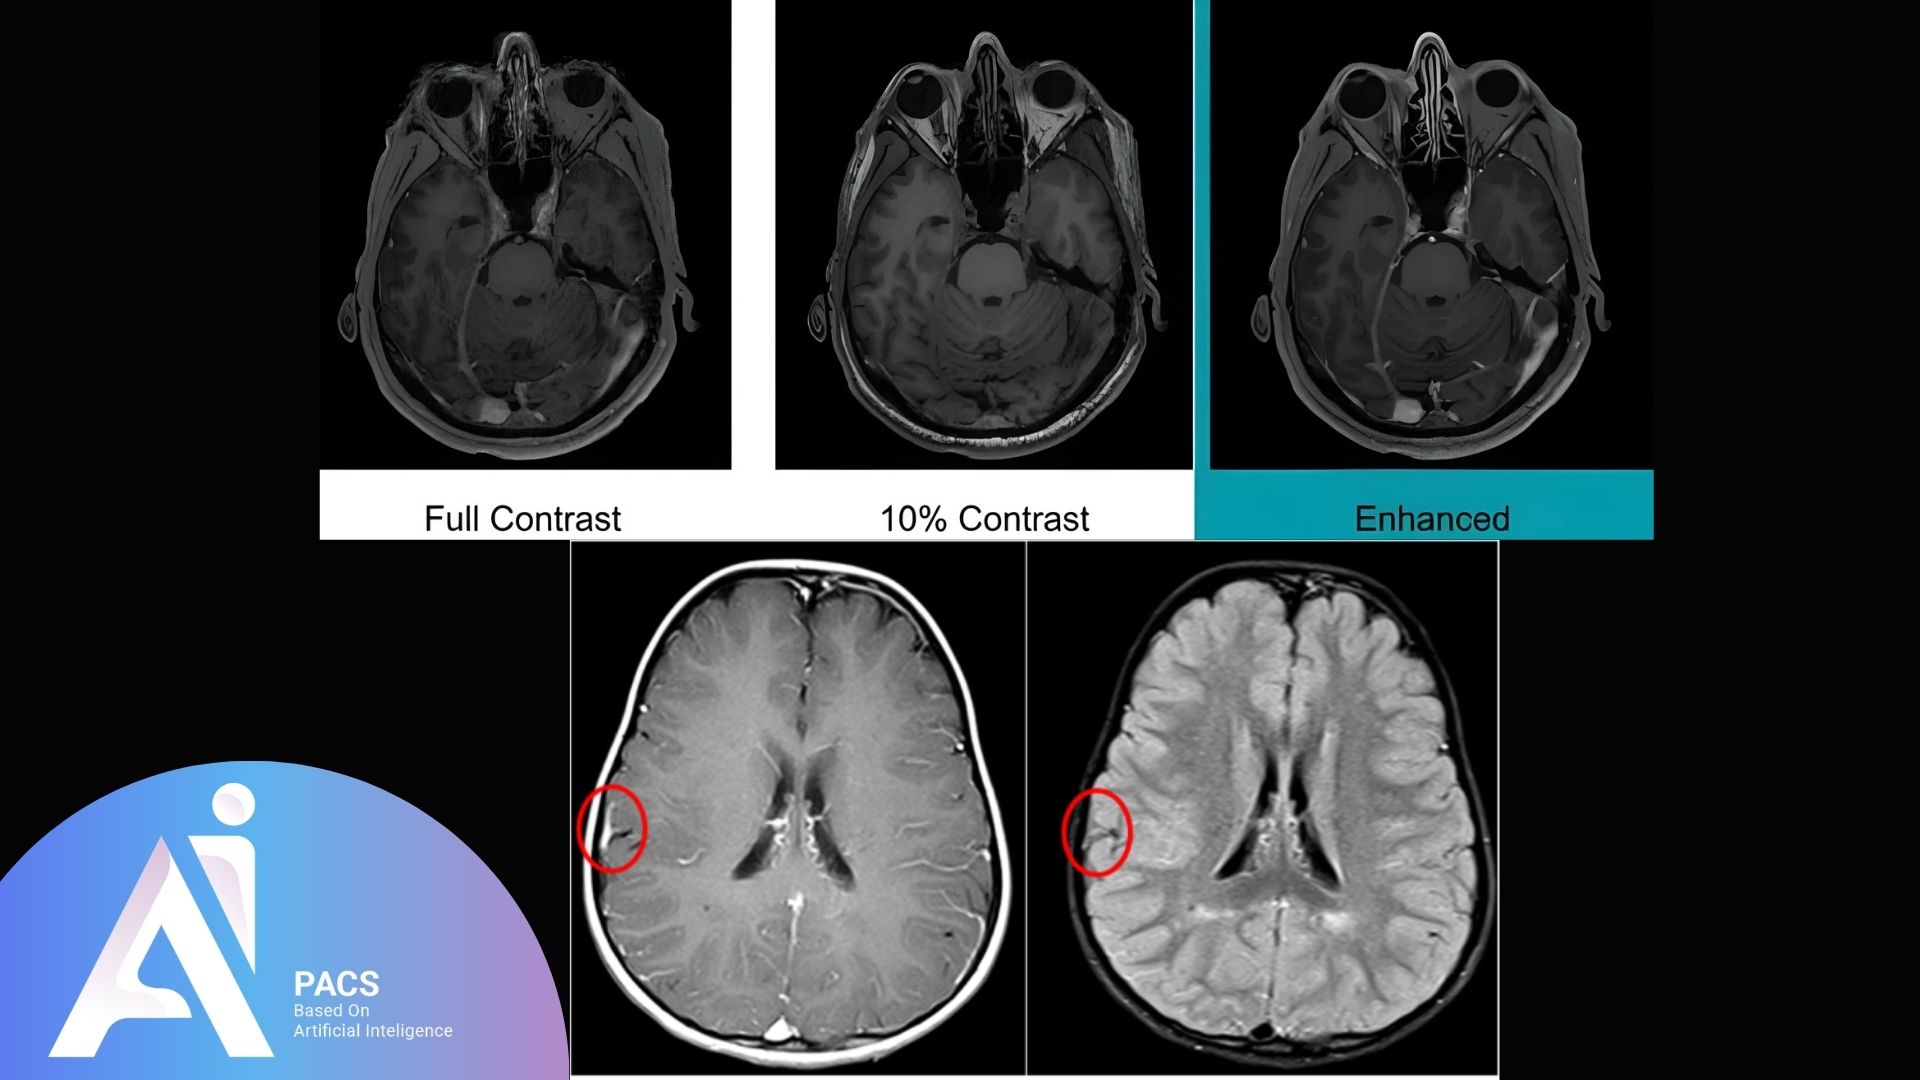

Importance of contrast in MRI

Contrast agents play a crucial role in enhancing the diagnostic capabilities of Magnetic Resonance Imaging (MRI). They improve the visibility of internal structures, helping radiologists differentiate between healthy and abnormal tissues. By providing greater detail in images, contrast agents facilitate the identification of tumors, inflammation, and vascular issues, leading to more accurate diagnoses and treatment planning. Furthermore, they enable the assessment of complex anatomical regions and conditions, making MRI a vital tool in modern medicine.

Contrast enhancement in MRI refers to using contrast agents to improve the clarity and detail of images the MRI machine produces. These agents, typically containing gadolinium, alter the magnetic properties of nearby tissues, allowing for better differentiation between various structures in the body. When injected into the bloodstream, contrast agents enhance the visibility of blood vessels and highlight areas of abnormal tissue, such as tumors or lesions. This enhancement helps radiologists assess the extent of diseases, monitor treatment responses, and make informed clinical decisions.